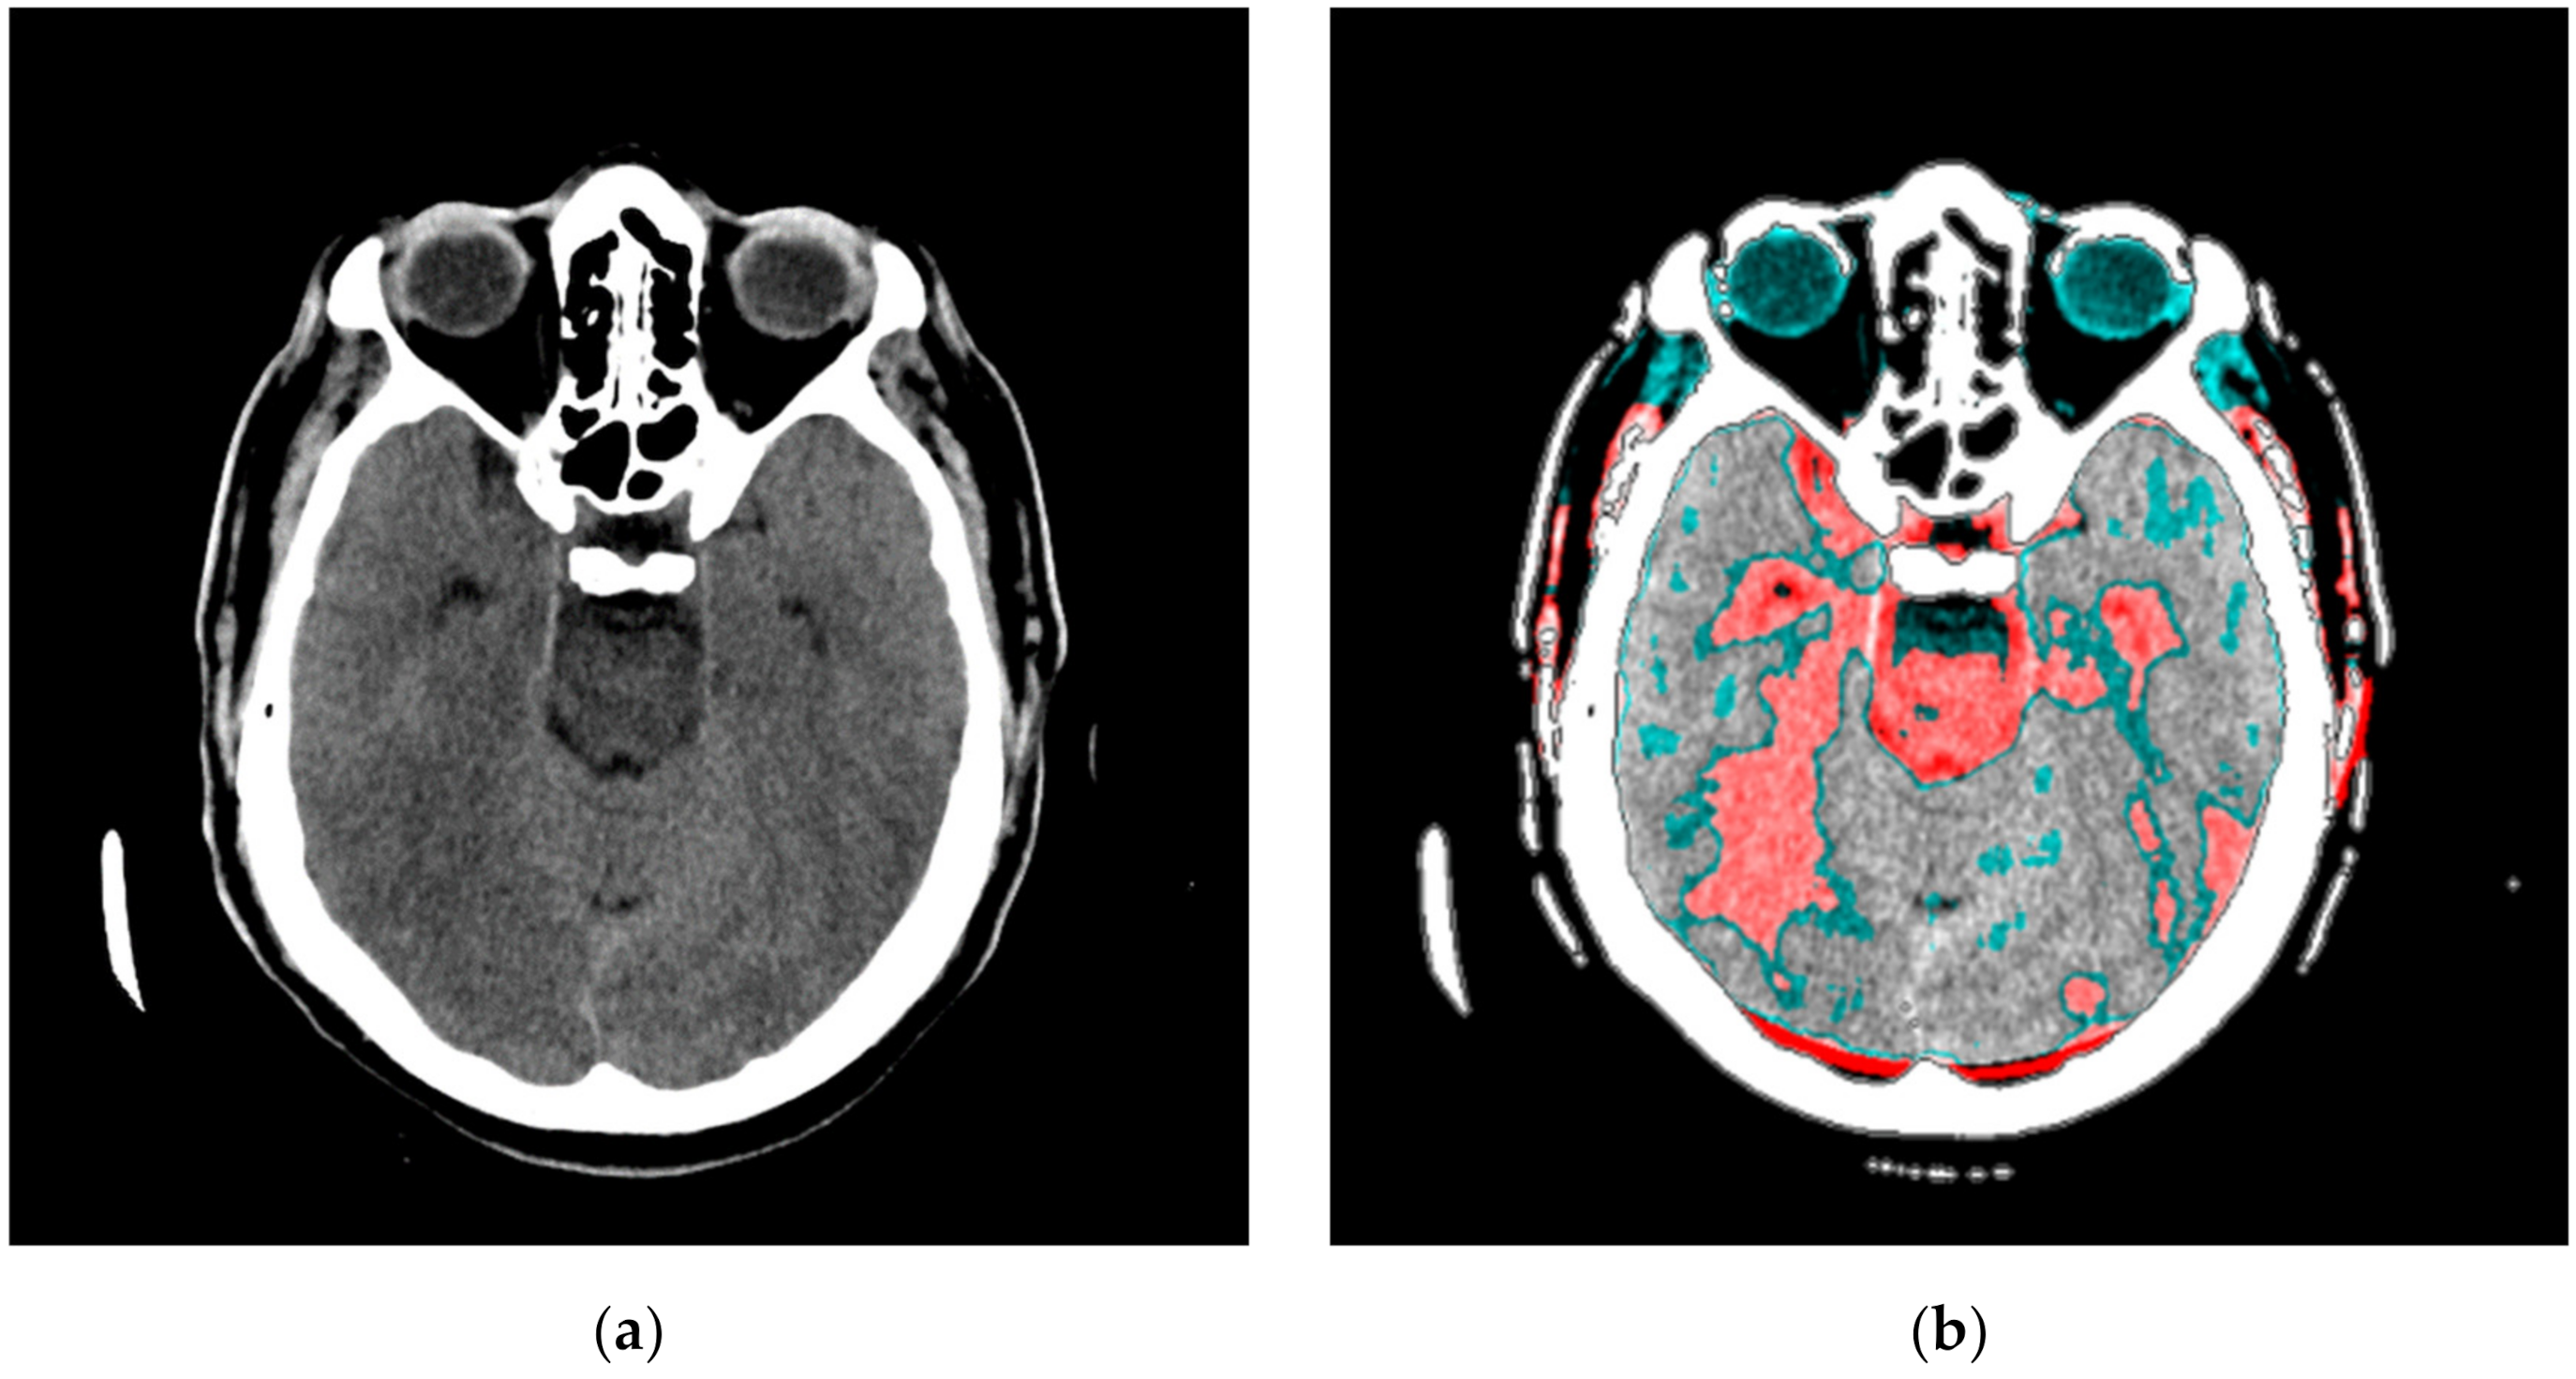

In our research approach, in marking content and regions of interest all values that do not contribute to the content are set to a pixel value of zero. In this way, the levels of black (which have a value of zero or slightly greater than zero), white values (which have a maximum value), and values of gray that are not contained in the central part of the gray are set to zero so as not to interfere with the physician conclusion while observing the central segment. At the same time, white parts (for example, bones) do not affect the mean value of the observed part. The smart visualization and the summary of the system output of the developed SVMI model is shown in Figure 3.

Figure 3.

Summary of the system outputs.